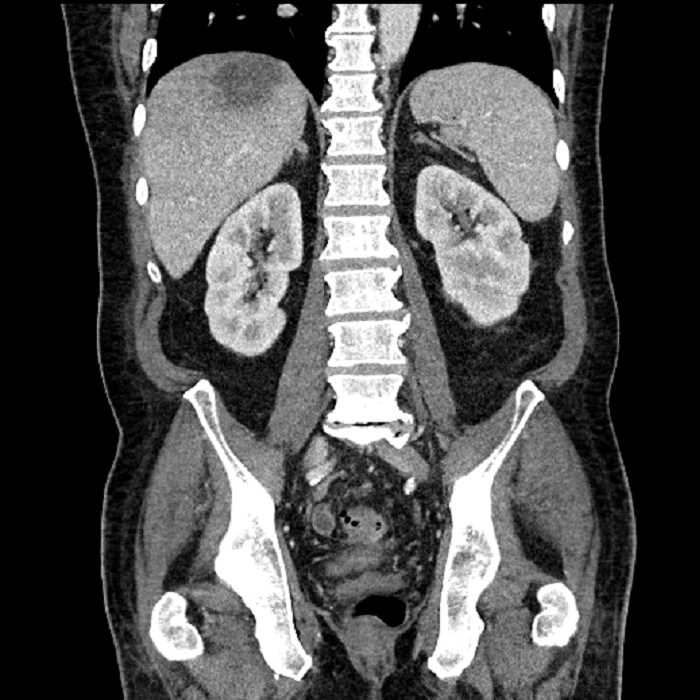

Age: 63

Sex: Male

Indication: Abdominal pain

• Large fluid density structure in hepatic segments 7 and 8 measuring 10 x 7 x 7 cm with internal septation and circumferential ill-defined low density compatible with edema

• Peripherally enhancing subcapsular collections along the anterior margin of the left hepatic lobe measuring 3 x 1 cm and 2 x 1 cm

• Clearly marginated fluid density structure in segment 7 and several other scattered tiny hypodensities, which likely represent cysts

• Hepatic abscess

Acute sigmoid diverticulitis complicated by a small contained perforation and a large abscess in the right hepatic lobe. Additional small subcapsular abscesses along the anterior margin of the left hepatic lobe.

• The classic CT imaging appearance is a double target sign with internal low density surrounded by an internal enhancing rim (capsule) and a low density external rim (edema)

Hepatic abscess showing the double target sign with low density internally surrounded by a thin inner enhancing rim (red arrow) and ill-defined outer low density rim (yellow arrow). Blue arrow indicates an internal septation. Red arrows: additional smaller subcapsular abscesses. Red arrow: focal contained perforation associated with diverticulitis.